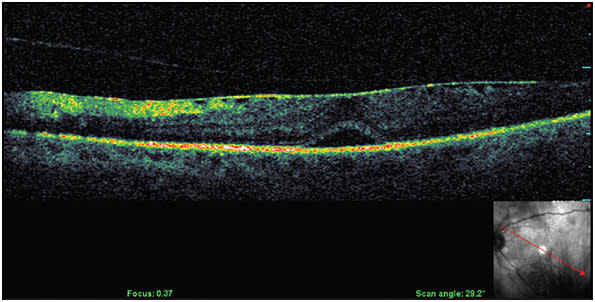

It is vital to rule out the presence of any vitreomacular interface abnormality, such as VMT and/or ERM, when examining patients with DME. This exclusion can be accomplished using optical coherence tomography (Figure 4) and slit-lamp biomicroscopy.

Figure 4. DME presenting with epiretinal membrane causing thickening of the macula and focal disturbance of the inner retinal layer.